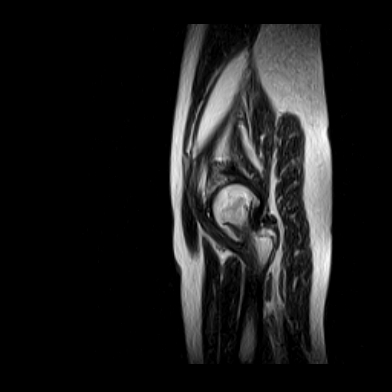

片子不全,应该是左侧股骨头无菌坏死,右侧似乎没问题,到正规医院治疗,千万别看广告去小医院,吃中药什么的,都是骗人的(说了也白说,百分百都得让人骗点钱才甘心。)

应该是左侧股骨头无菌坏死